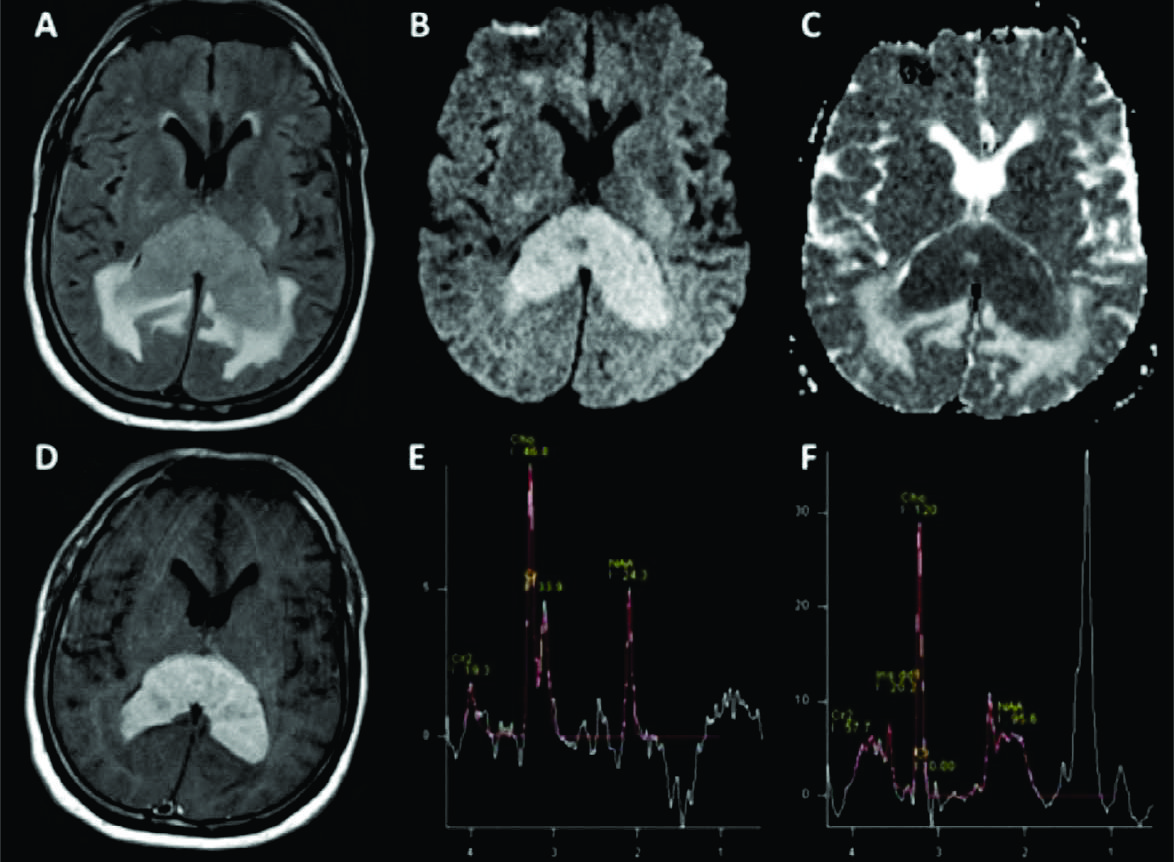

Figura 1

LPSN multifocal con compromiso del cuerpo calloso.

Paciente con diagnóstico de LPSN con múltiples focos de realce, el principal en el CC, sector posterior. Se observa el comportamiento más frecuente: hipointensidad en T1 (A), hipointensa en T2 con respecto a la SG cerebral (B), con edema asociado en FLAIR (C) y restricción en difusión (D). Con el medio de contraste se observa el intenso y homogéneo realce con bordes irregulares (E) y al menos 2 focos adicionales en la sustancia blanca subcortical del lado izquierdo (F).

Figura 6

LPSN clásico con compromiso del CC, espectroscopía.

Pacientes con una típica lesión de CC hiperintensa en FLAIR (A) con edema, restricción en difusión (B) y ADC (C) e intenso realce homogéneo con el contraste (D). Los trazados metabólicos obtenidos muestran en eco largo (E) un ascenso de Ch con descenso de NAA que confirma la naturaleza tumoral de la lesión.

En el tiempo de eco corto (F) se mantiene este hallazgo y se hace evidente un significativo pico de Lip/Lac típico de estas lesiones, sin mioinositol.

Este patrón fue el obtenido en la mayoría de las lesiones de esta serie.